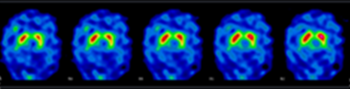

Exemples d’images obtenues par le service de Médecine Nucléaire de l’hôpital de Citadelle